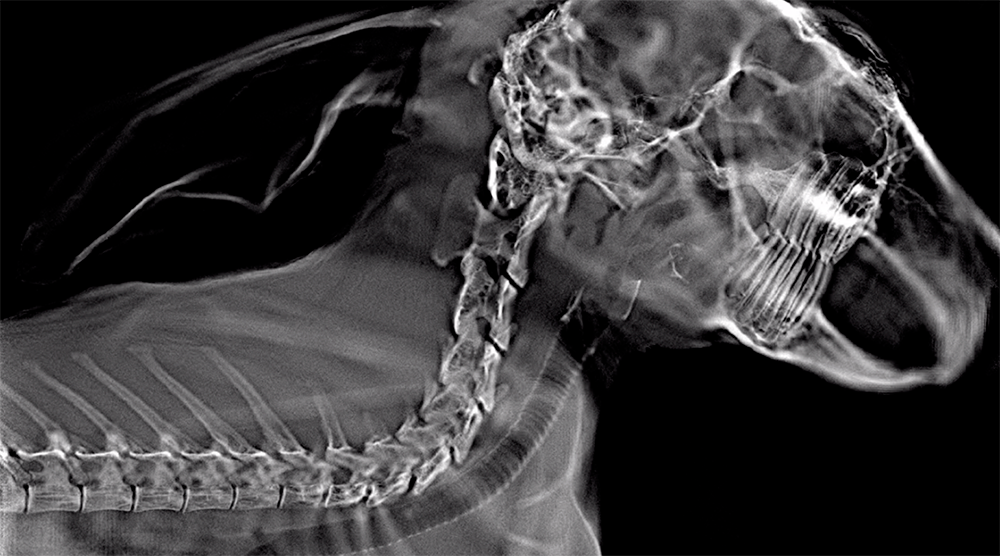

Adaptix, based at Oxford University Science Park, is driven by a mission to transform radiology by offering affordable low-dose 3D (‘Digital Tomosynthesis’ or ‘DT’) imaging at the point-of-care.

Adaptix is already serving veterinary and industrial (Non-Destructive Evaluation) markets using its novel and patent-protected technologies. Receiving the 510(k) clearance is important as it is the first step in Adaptix delivering its mission to transform radiology through provision of innovative truly-portable 3D imaging technologies into healthcare providers.